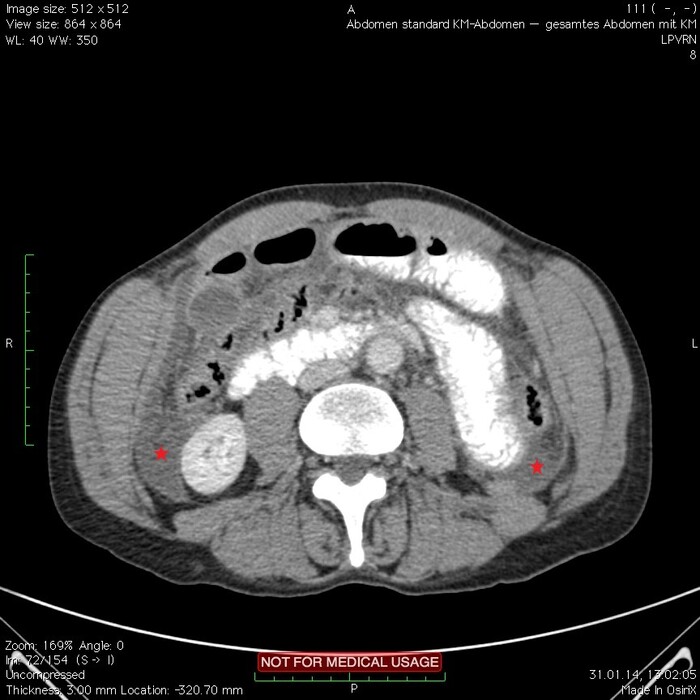

Мужчина, 32 года. Во время игры в футбол получил удар в низ живота, игру продолжил. Впоследствии боли в животе усиливались, стали нестерпимыми, ухудшилось общее самочувствие. На следующий день после игры пошёл сдаваться в больницу. Хирурги клинически описывают разлитой перитонит (воспаление брюшины) и отсылают пациента к нам на КТ, которое мы провели с внутривенной дачей контраста + заставили контраст ещё выпить (специальный раствор для перорального применения).

Верхние (проксимальные) отделы точно не причём. Жидкость (звёздочки) больше в малом тазу, тут же и воздух. Для сравнения верхний этаж:

Hижний этаж: